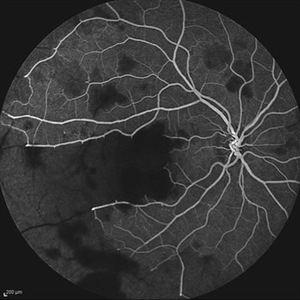

Idiopathic Occlusive Retinal Vasculitis (Late Stage) Idiopathic Occlusive Retinal Vasculitis (Late Stage)May 31 2014 by Hamid Ahmadieh, MD Late phase FA image of the right eye of a 28-year-old woman with idiopathic occlusive retinal vasculitis 6 months after the onset. Photographer: Solmaz Shahmohammad, Negah Eye Center, Tehran Imaging device: Heidelberg Spectralis Condition/keywords: capillary closure, fluorescein leakage, macular infarction